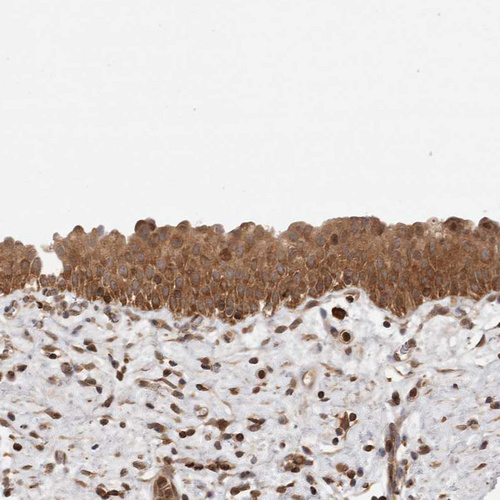

Immunohistochemistry analysis in human lymph node and cerebral cortex tissues using HPA027305 antibody. Corresponding NFKB1 RNA-seq data are presented for the same tissues.